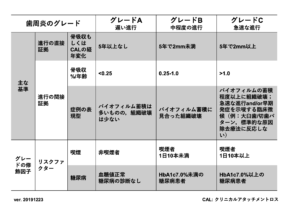

上記は、日本歯周病学会の歯周病の新分類の指標になりますが、

『歯周病の重症度』をステージ分類し

『歯周病の進行のスピード』をグレード分類します。

少し難しいお話かもしれませんが、診断は人によって違うため、患者様一人一人の状態に合わせて治療方針と治療計画を立てる必要性があるということです。